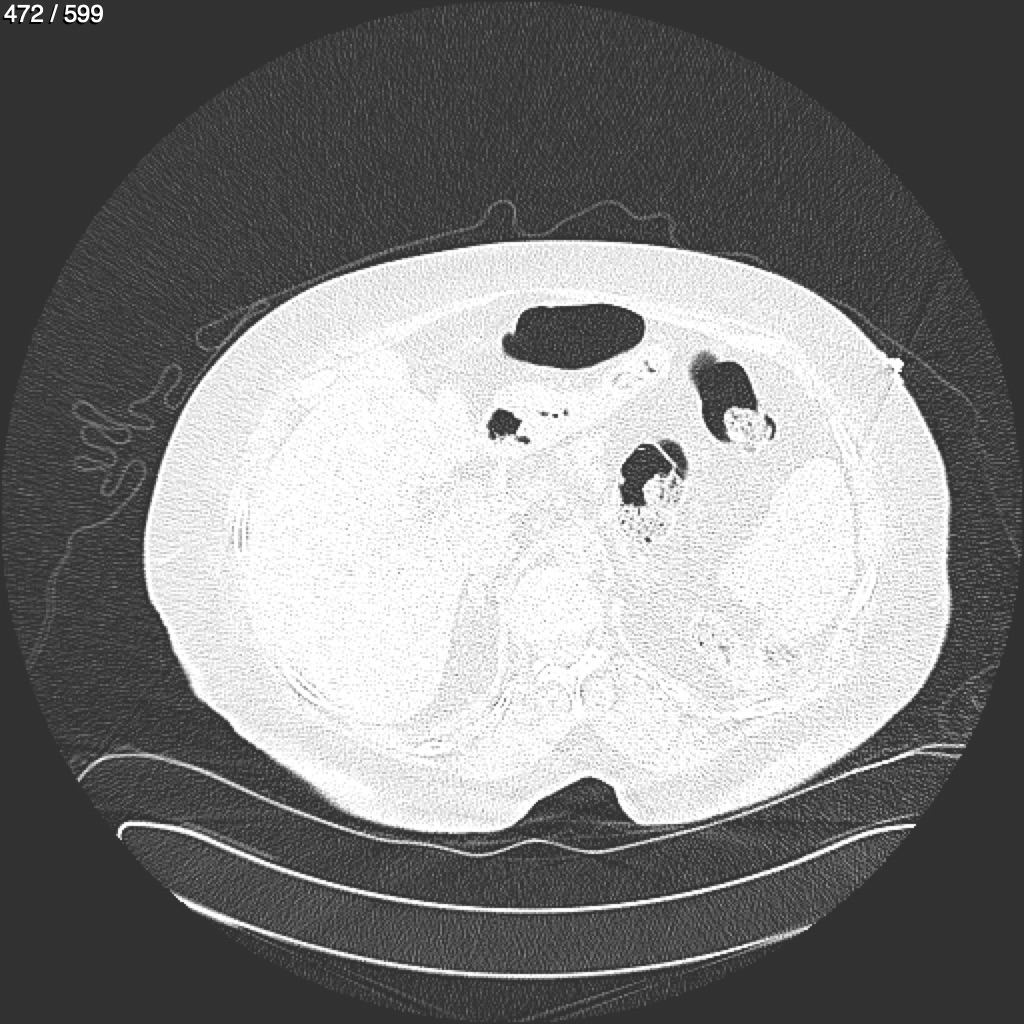

Home G​l​o​r​i​a​ ​G​l​a​d​y​s​ ​B​e​a​s​l​e​y​ ​-​ ​T​ó​r​a​x​ ​T​o​r​a​x​_​S​i​m​p​l​e​ ​(​A​d​u​l​t​o​)